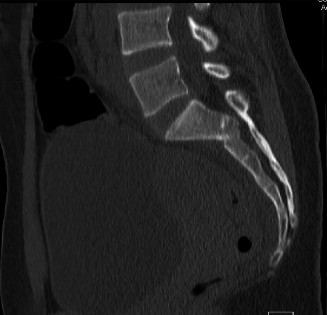

Expected surgical outcomes following revision surgery for recurrent disc herniation? CASE 3 A 27-year-old previously healthy woman is transferred directly to your trauma center with severe low back pain after jumping from an overpass in an apparent suicide attempt. The trauma team completes the primary survey, and the patient is hemodynamically stabilized with fluid resuscitation. On secondary survey she is found to have significant pain with examination/manipulation of her pelvis. Lower extremity examination demonstrates multiple superficial abrasions and grade 4/5 strength with great toe extension and ankle dorsiflexion on the left. Inspection of the perineum shows no blood at the urethral meatus or rectum; however, rectal tone and perianal sensation are decreased. The remainder of the examination is unremarkable. An anteroposterior view of the pelvis demonstrates unilateral superior and inferior rami fractures and a right L5 transverse process fracture.

The correct answer is (C). It is important to recognize that plain radiographs may only detect 30% of sacral injuries. This patient’s plain x-ray findings are highly suggestive of more substantial injuries than isolated rami fractures and transverse process fractures. In fact, the transverse process fracture should be assumed to have occurred by avulsion via the lumbosacral ligaments, which suggests large displacement of the hemipelvis. While plain radiographs may demonstrate sagittal displacement of sacral fractures, they are often of poor quality and do not enable

delineation of the entire fracture pattern. A pelvic computed tomography (CT) scan is indicated to better evaluate the bony injury as well as canal encroachment, particularly in the setting of a neurological deficit. An angiogram might be indicated if the patient was hemodynamically unstable and an intrapelvic bleed was suspected. CT scan images of the above patient are shown inFigures 1–8 and 1–9. Definitive management of this injury should be: 1. 3 months of bed rest followed by progressive mobilization

Figure 1–8 Mid-sagittal image of the pelvis.

The correct answer is (D). Critical steps in decision-making include determination of neurologic status, presence of associated pelvic ring injuries, and stability of the lumbopelvic junction. The neurologic examination demonstrates a deficit that is at least in part localized to the sacral nerve roots. In the presence of sacral canal compromise, decompression via laminectomy is indicated. The CT scan demonstrates a U-type injury with a high transverse sacral fracture and bilateral vertical extension through the sacral foramen. In the descriptive classification of sacral fractures in Denis zone 3, H-type and U-type sacral fractures represent spinopelvic dissociation and must be distinguished from fractures localized to the posterior pelvic ring, which are vertically unstable. The spinopelvic junction serves as a critical transitional zone as the axial load of the upper body is distributed from the upper sacrum to the ilium and finally the acetabulum. Surgery is indicated to prevent progressive deformity and chronic pain. Reconstruction should include stabilization from the lumbar spine to the pelvis using a pedicle screw/iliac screw construct. Nonoperative treatment with progressive mobilization is not appropriate for this type of fracture. Plating of the sacrum is not sufficient to restore stability of this injury; nor are sacroiliac screws.